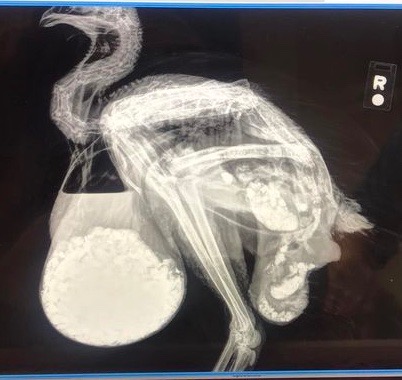

What is going on with this bird? – Leigh Ann

Dr Bowes: This is a case of pendulous crop caused by the ingestion of a large amount of what looks like non-food material (e.g. gravel). I’m curious as to what is causing the bulge past the hock and the cluster at the base. Is that a hernia? There is no cure for this condition. I would recommend humane euthanasia.

That is one amazing X-ray…poor thing.